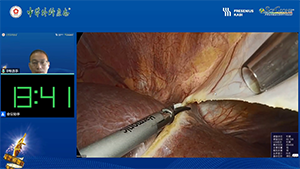

腹腔镜原位解剖性右半肝切除术治疗初始不可切除肝癌

作者:陶海粟 | 作者单位:南方医科大学珠江医院